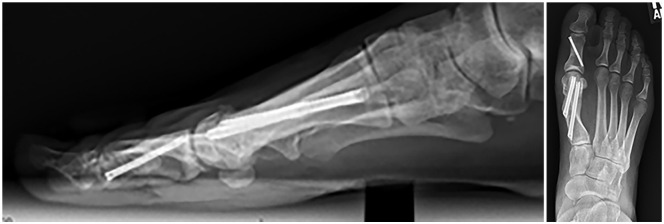

Methods: We retrospectively analyzed 217 consecutive patients with moderate to severe hallux valgus who underwent fourth-generation MIS first distal metatarsal and Akin osteotomy between 2020 and 2023 and were followed for up to 1 year. Radiographic measurements included the scale of displacement between the proximal and distal portions of the first metatarsal as a percentage and the number of neocortical bridge formations at the osteotomy site. Postoperative weightbearing radiographs were recorded at 6 weeks, 3 months, 6 months, and 1 year to assess time to union and patient clinical outcomes. Two orthopaedic surgeons independently reviewed the radiographs to assess progression to bony union. Any discrepancy in analysis was resolved by a third-party clinician. Complete union was defined as the presence of at least 2 new cortical bridge formations on postoperative X-ray films. Patients were divided into 3 groups based on the percentage of shift on the first metatarsal head (≤50%, 51%-75%, ≥76%) for the purpose of our analysis.

Results: Union (≥2 cortices) was observed in 17%, 70%, and 90% of patients at 6 weeks, 3 months, and 6 months, respectively. At final follow-up (mean 13 ± 6.9 weeks), 92% achieved union. No significant differences in time to union were observed across metatarsal shift groups.Complications include 3 nonunions, 3 revisions, 16 cases that necessitated removal of hardware, 1 case of superficial wound infection, 1 case of deep wound infection, and 6 deformity recurrences.

Conclusion: Time to union after META procedure typically occurred by 13 weeks, independent of shift magnitude. Surgeons may consider ≥2 cortices and absence of symptoms as sufficient indicators for advancing weightbearing. These findings may assist in patient counseling and postoperative planning.Level of Evidence: Level IV, retrospective case series.